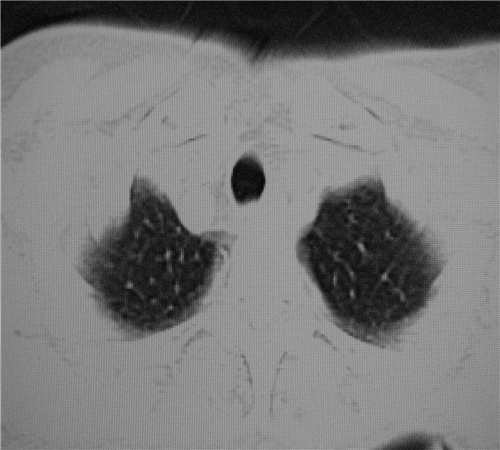

标题: CT26849:女67岁反复胸痛两天余,临床考虑夹层。 [打印本页]

标题: CT26849:女67岁反复胸痛两天余,临床考虑夹层。

右肺感染,未见夹层。

既然考虑夹层,建议强化!另:右下肺感染!

1)右肺感染性病变。2)建议行ct增强扫描或mri检查排除主动脉夹层。

双下肺感染,右侧显著。有无夹层,增强扫描后再诊断。